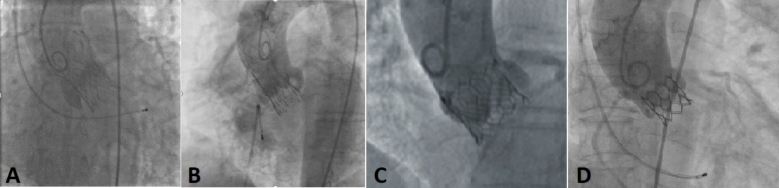

Abstract Image